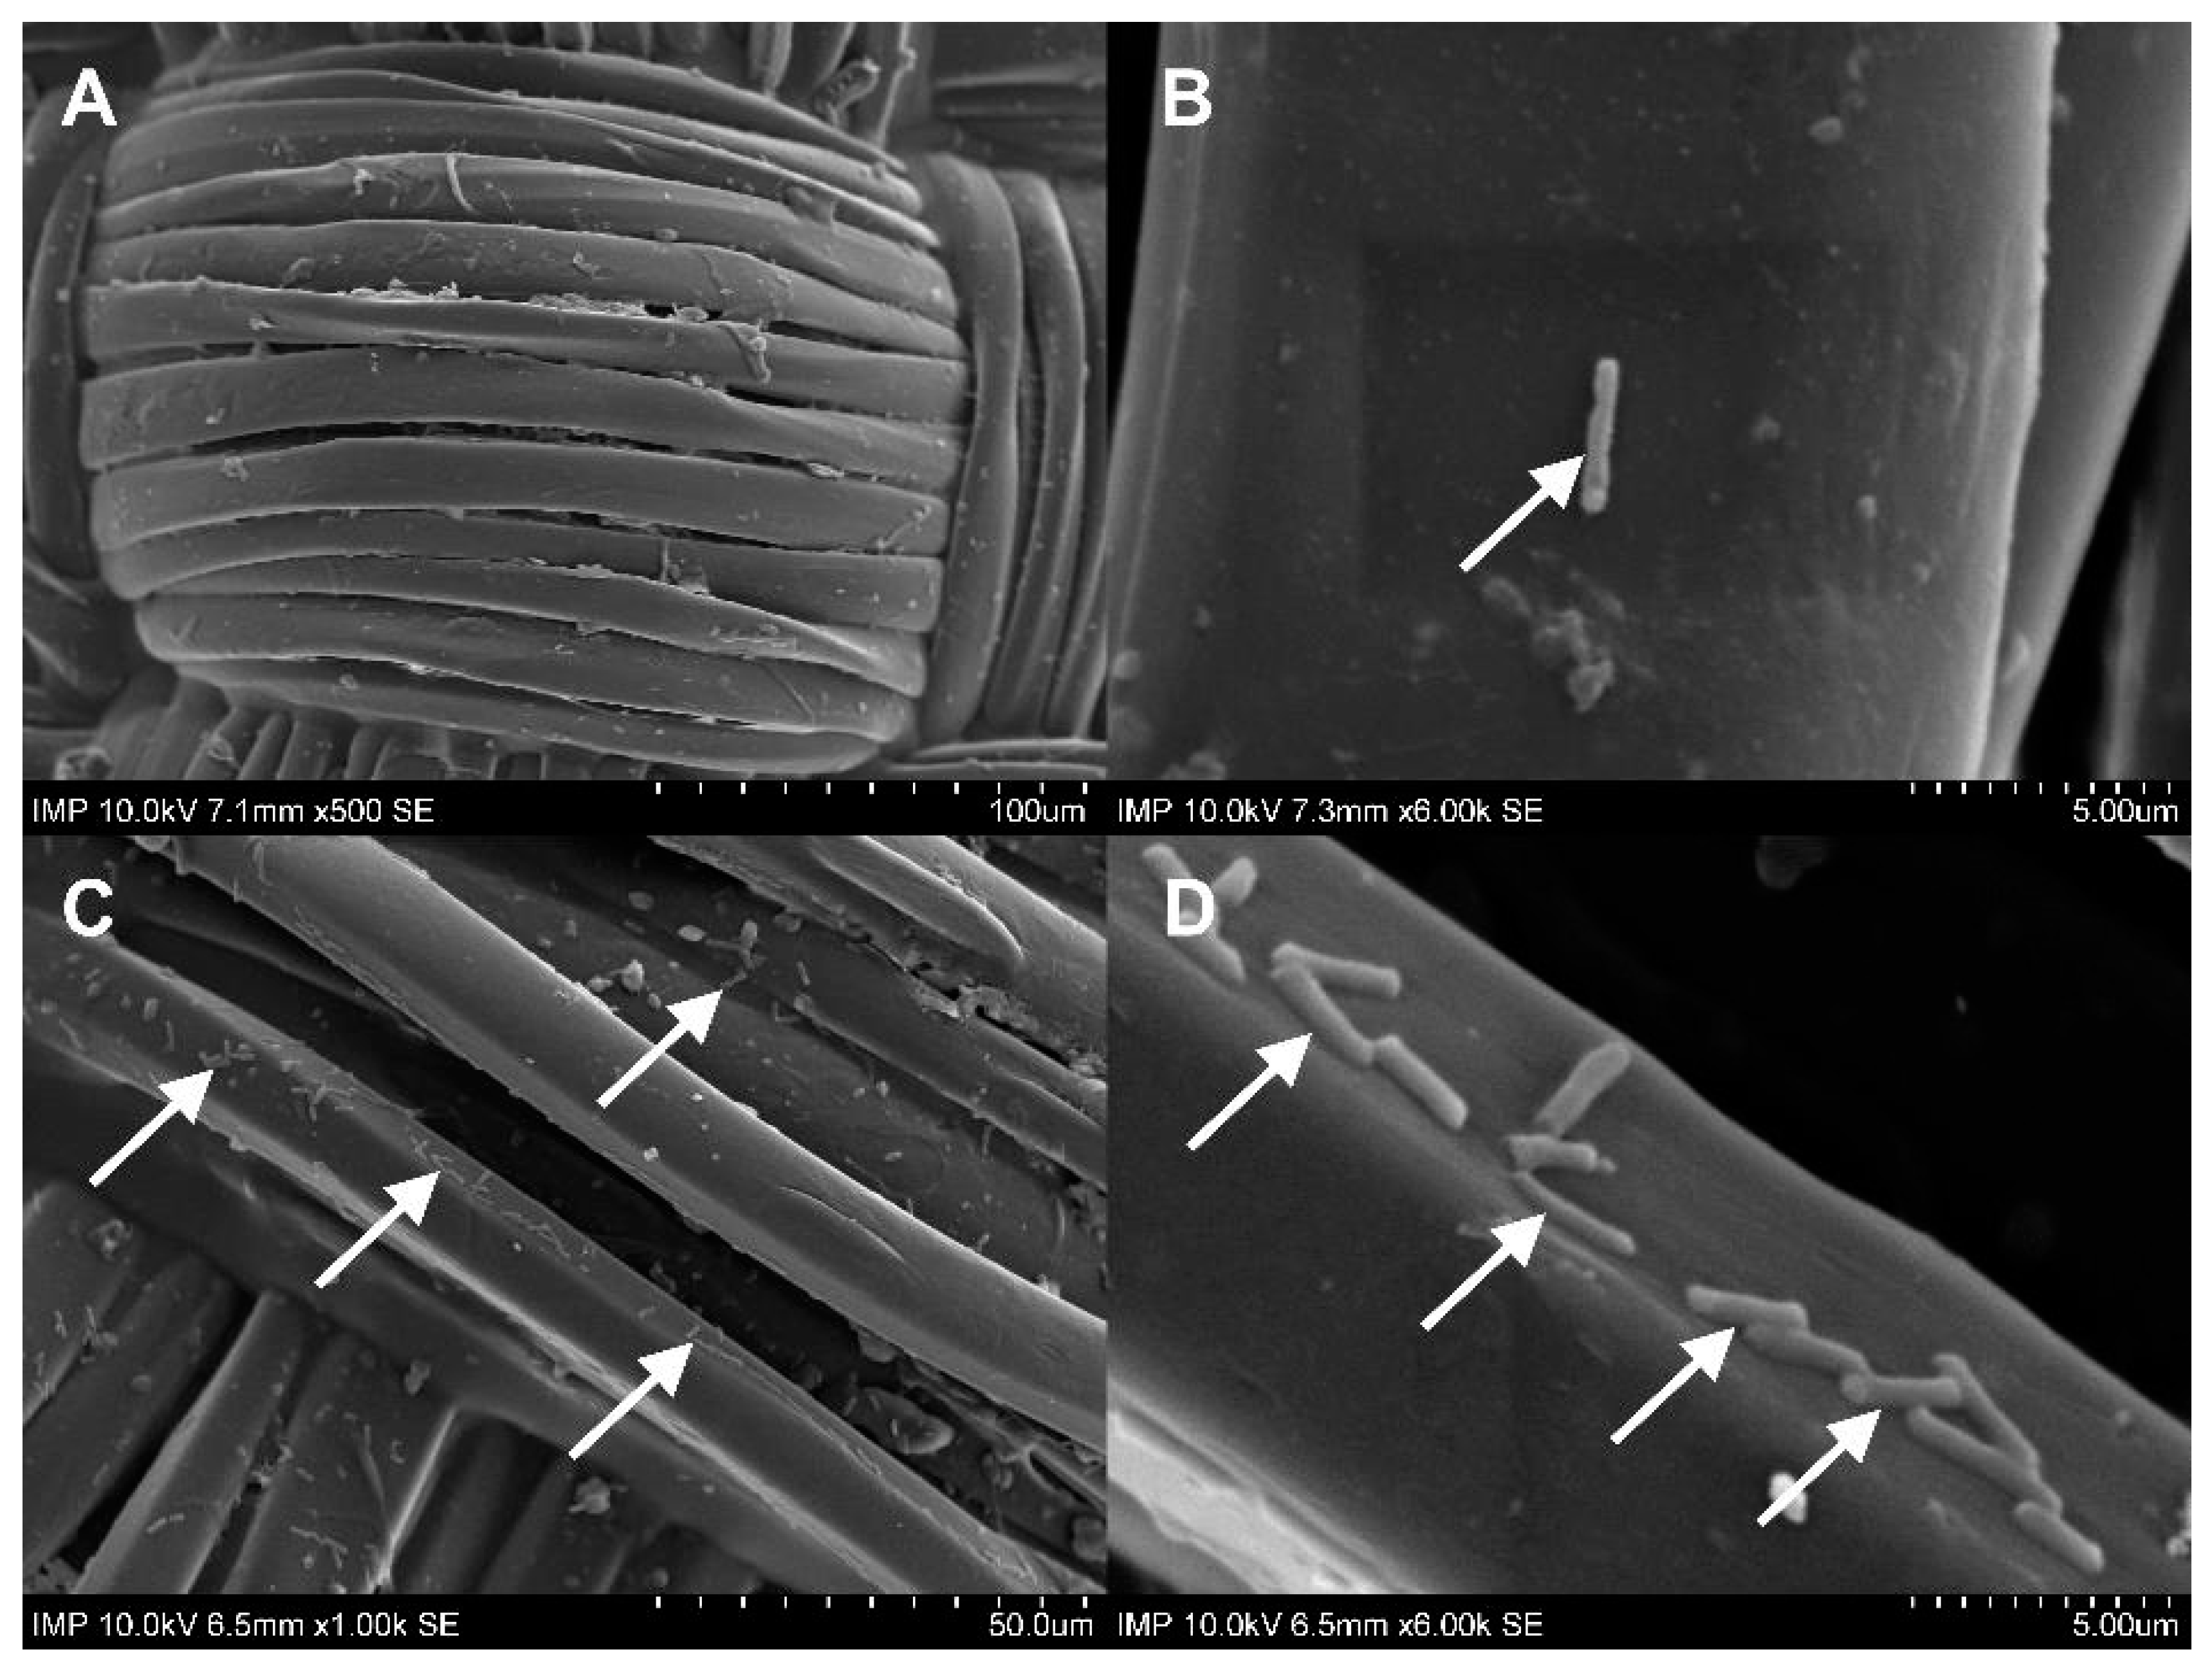

2.1. Surface Coating of the Grafts

2.4. Antibacterial Activity against Recurrent Contamination

4.2.5. Scanning Electron Microscopy